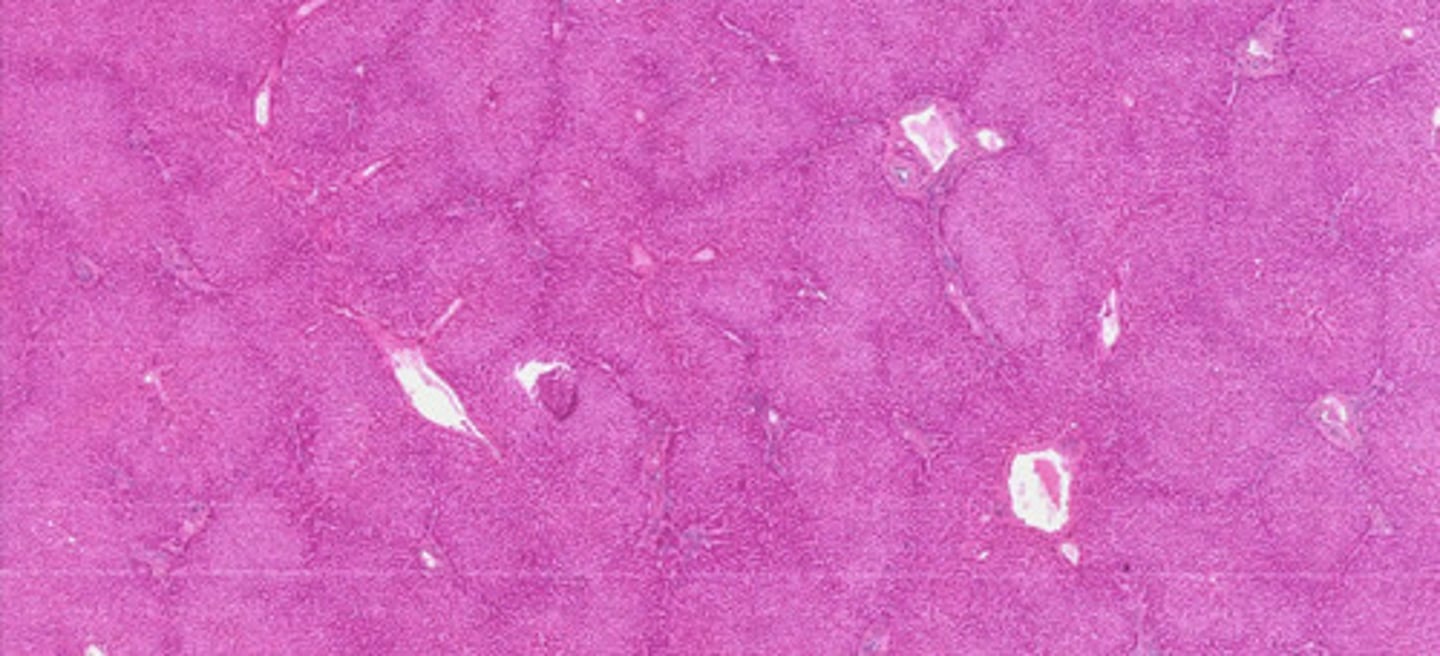

Wątroba ludzka (H+E)

Wątroba ludzka (met. Mallory)

Wątroba - komórki Browicza-Kupffera

(barw. błękitem trypanu)